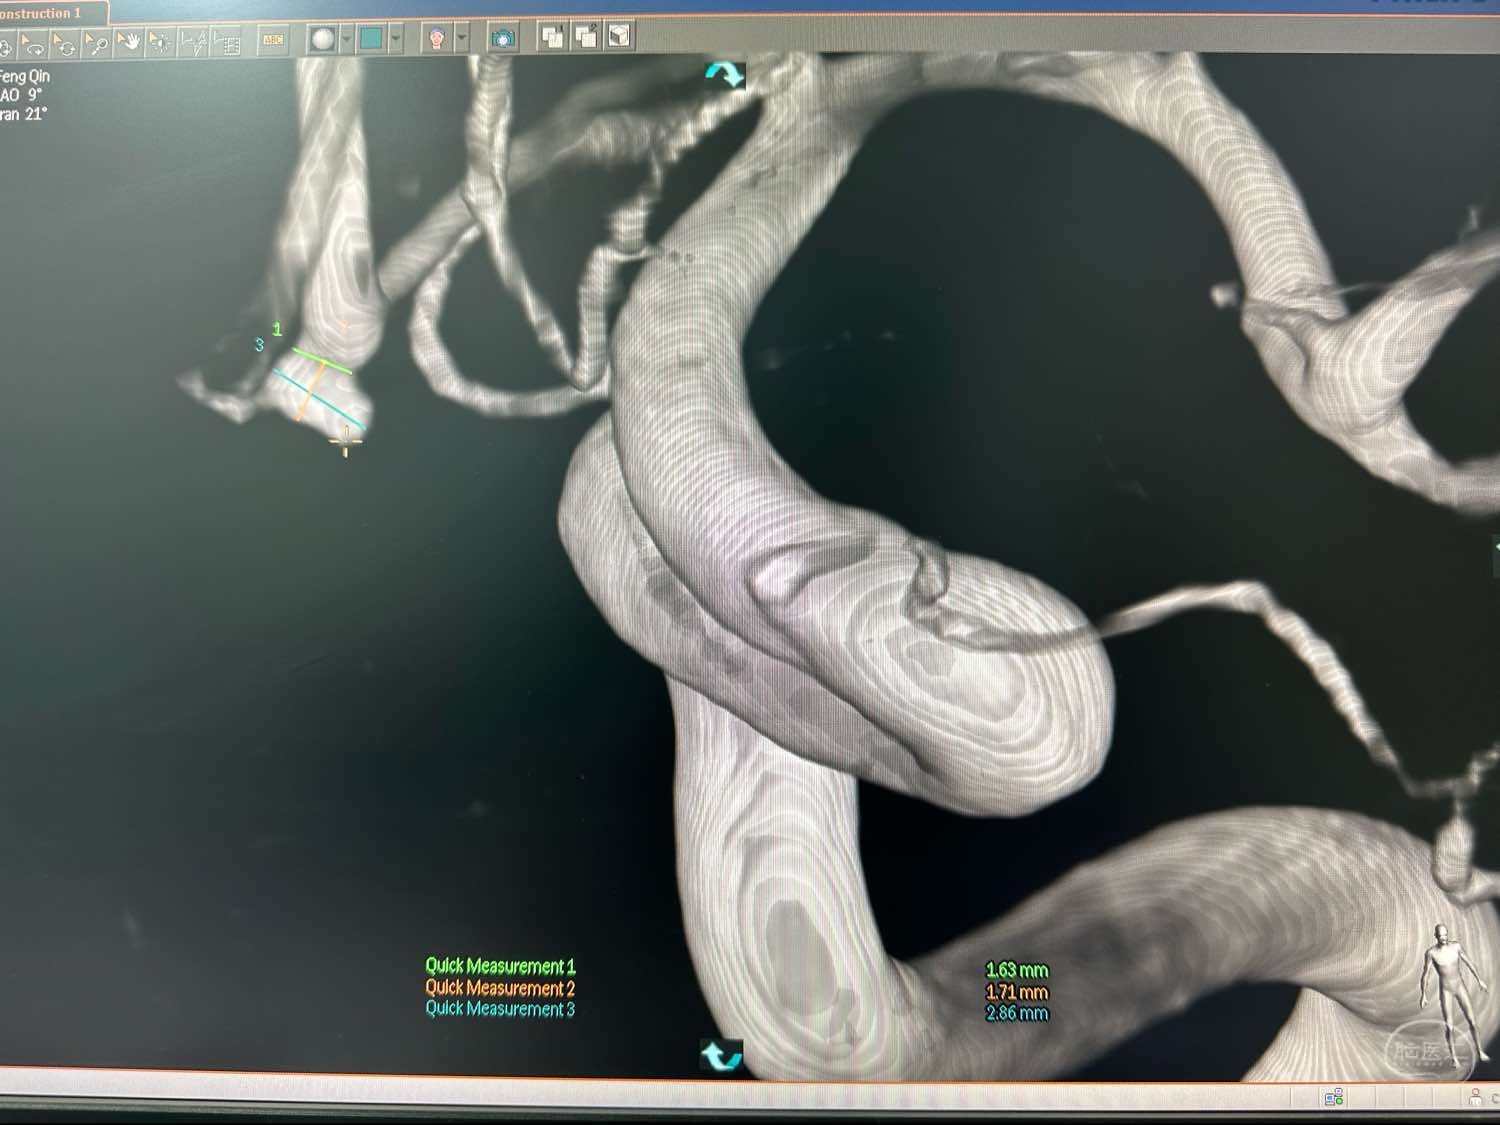

左侧颈内动脉造影3D